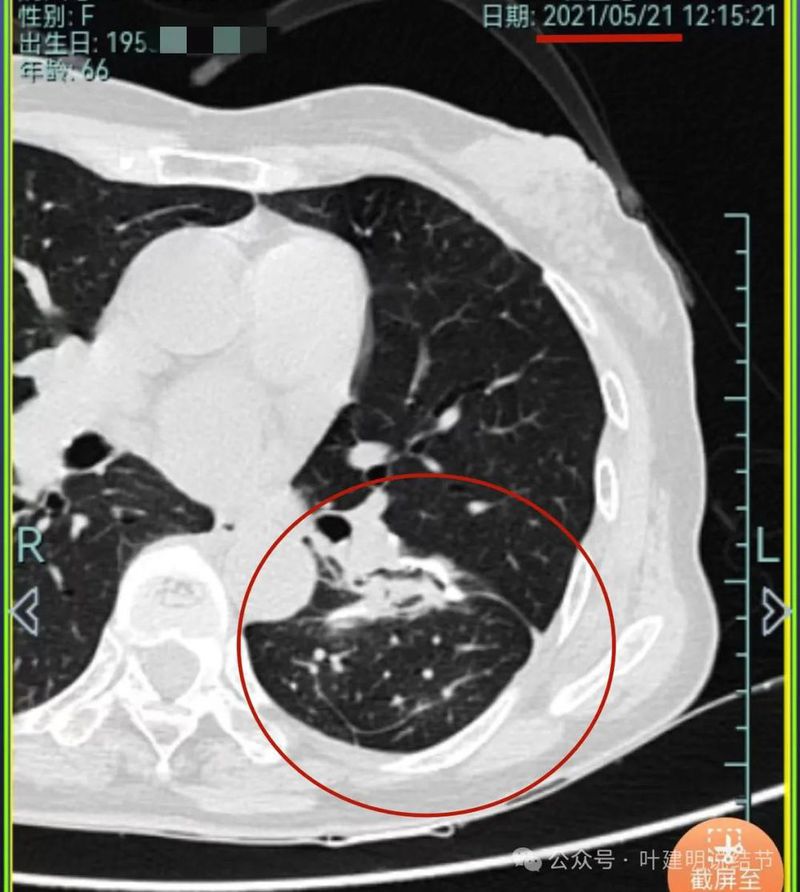

再看2021年随访的影像:

病灶1似乎中间高密度部分略有密度增高。

病灶2与2019年时相仿。

病灶3仍是混合密度,进展不显著。

病灶4仍是伴钙化的,也没有明显进展。

病灶5较前密度略显杂乱,整体密度应该有所增高。

病灶6轮廓较前清楚,灶内有血管穿行,也有轻微胸膜牵拉。

原病灶7已经被切除。